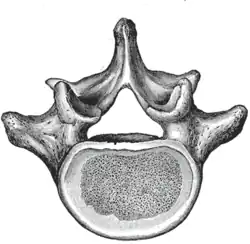

The adjacent figure depicts the general characteristics of the first through fourth lumbar vertebrae. The fifth vertebra contains certain peculiarities, which are detailed below.

As with other vertebrae, each lumbar vertebra consists of a vertebral body and a vertebral arch. The vertebral arch, consisting of a pair of pedicles and a pair of laminae, encloses the vertebral foramen (opening) and supports seven processes.

The vertebral body of each lumbar vertebra is kidney shaped, wider from side to side than from front to back, and a little thicker in front than in back. It is flattened or slightly concave above and below, concave behind, and deeply constricted in front and at the sides.[1]

The vertebral foramen within the arch is triangular, larger than the thoracic vertebrae, but smaller than in the cervical vertebrae.[1]

3D image of a lumbar vertebra